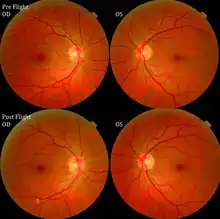

The first U.S. case of visual changes observed on orbit was reported by a long-duration astronaut that noticed a marked decrease in near-visual acuity throughout his mission on board the ISS, but at no time reported headaches, transient visual obscurations, pulsatile tinnitus or diplopia (double vision). His postflight fundus examination (Figure 1) revealed choroidal folds below the optic disc and a single cotton-wool spot in the inferior arcade of the right eye. The acquired choroidal folds gradually improved, but were still present 3 year postflight. The left eye examination was normal. There was no documented evidence of optic-disc edema in either eye. Brain MRI, lumbar puncture, and OCT were not performed preflight or postflight on this astronaut.[5]

The sixth case of visual changes of an ISS astronaut was reported after return to Earth from a 6-month mission. When he noticed that his far vision was clearer through his reading glasses. A fundus examination performed 3 weeks postflight documented a grade 1 nasal optic-disc edema in the right eye only. There was no evidence of disc edema in the left eye or choroidal folds in either eye (Figure 13). MRI of the brain and eyes days postflight revealed bilateral flattening of the posterior globe, right greater than left, and a mildly distended right optic nerve sheath. There was also evidence of optic-disc edema in the right eye. A fundus examination postflight revealed a "new onset" cotton-wool spot in the left eye. This was not observed in the fundus photographs taken 3 weeks postflight.[5]

The seventh case of visual changes associated with spaceflight is significant in that it was eventually treated postflight. Approximately 2 months into the ISS mission, the astronaut reported a progressive decrease in his near and far acuity in both eyes. The ISS cabin pressure, CO2 and O2 levels were reported to be within normal operating limits and the astronaut was not exposed to any toxic substances. He never experienced losses in subjective best-corrected acuity, color vision or stereopsis. A fundus examination revealed a grade 1 bilateral optic-disc edema and choroidal folds (Figure 15).[5]